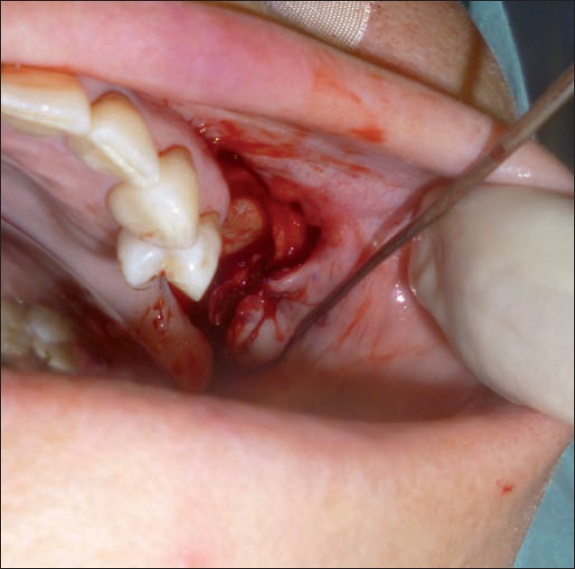

La paciente fue sometida a cirugía con mucosectomía del seno maxilar mediante abordaje de Cadwell-Luc, y cierre de la fístula con un colgado mucoperióstico vestibular de avance ( Fig. 3 y 4). Además, en el mismo acto operatorio, llevamos a cabo via abordaje vestibular inferior, incisión de la mucosa alveolar, desbridamiento del foco de osteonecrosis mandibular y cierre con colgajo local.